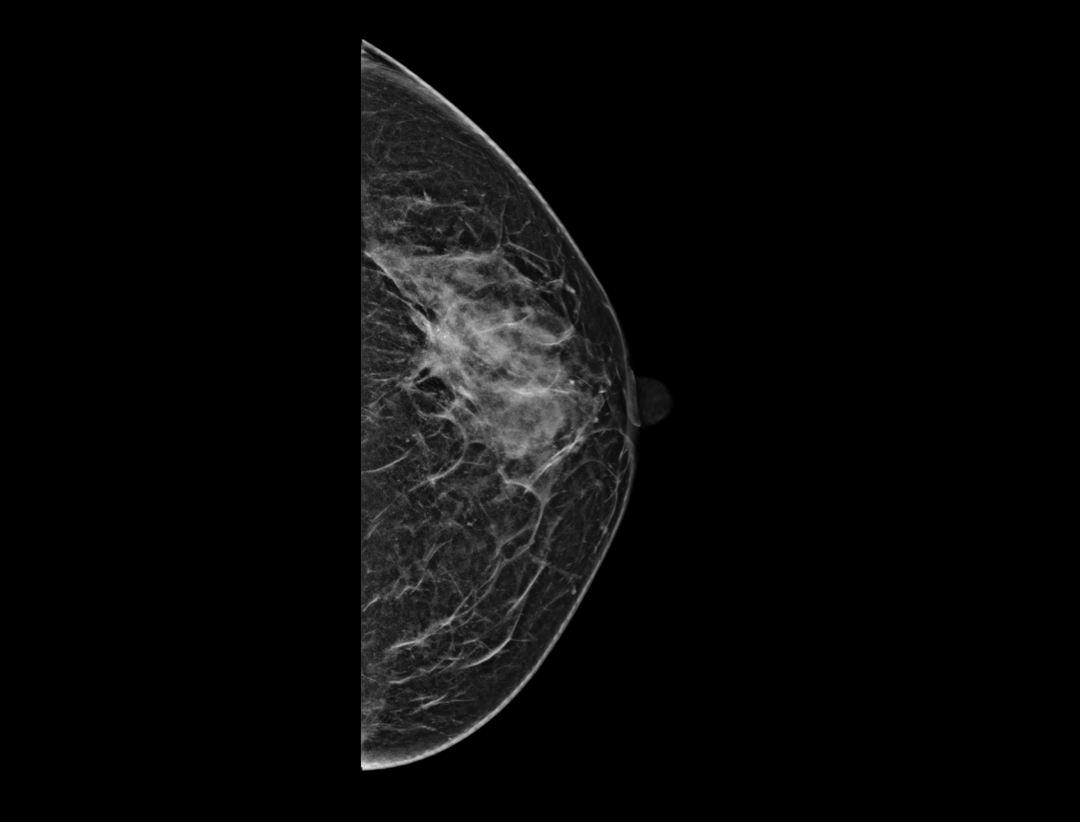

Adaptacyjne dostosowanie grubości warstwy tomosyntezy zapewnia szczegółowe obrazowanie przestrzenne zmian chorobowych i skupisk mikrozwapnień.

Wiele konfiguracji protokołów wyświetlania i wszechstronne narzędzia sprawiają, że przeglądanie mammografii cyfrowej jest bardziej elastyczne i uproszczone. Narzędzie lokalizatora pomaga użytkownikowi wskazać pozycje warstw tomosyntezy wewnątrz obrazu 3D.

Hybrydowe protokoły wyświetlania pozwalają na synchroniczne wyświetlanie obrazów 2D i warstw tomosyntezy w celu łatwego porównania. Dostępne są zarówno pogrubione warstwy (slabs), jak i widok płaszczyzny.